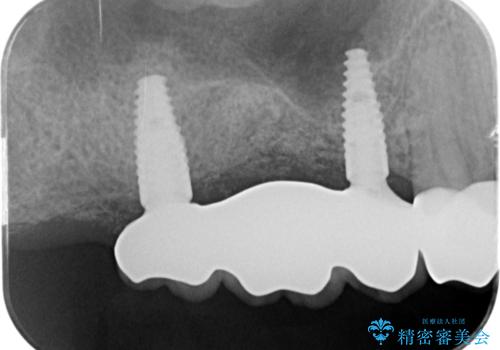

[メタルフリー] 虫歯・銀歯だらけの口腔内を全顎治療

銀歯の下には虫歯の再発が見られたり、根尖病変や歯周病、噛み合わせといった複合的な問題が認められます。

残すことのできる歯には根管治療・歯周病治療を行い、やむを得ず抜去の必要な部位はブリッジやインプラントを用い、安定した噛み合わせ・歯の磨きやすい環境を確立していきます。